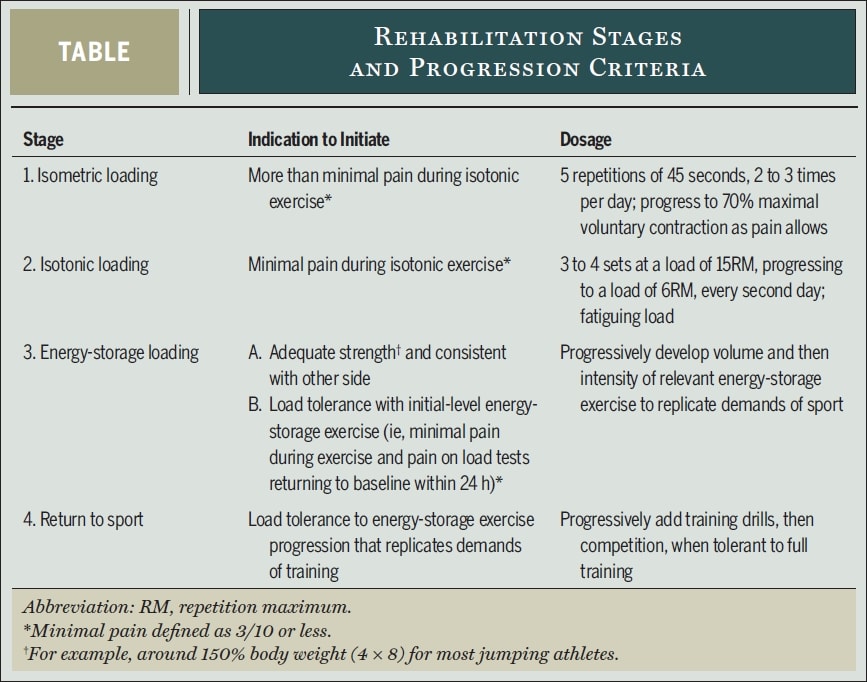

Come potrebbe essere un programma di resistenza pesante e lenta? I migliori ricercatori in materia di tendinopatia, Peter Malliaras, Jill Cook, Craig Purdam e Ebonie Rio, propongono il seguente protocollo di riabilitazione in 4 fasi, basato sull'evidenza, nel loro articolo pubblicato su 2015:

In primo luogo è necessario modificare il carico delle attività di accumulo di energia ad alto carico che aggravano il dolore. Nel caso di atleti a metà stagione, il volume e la frequenza di tali attività devono essere ridotti in consultazione con l'atleta e l'allenatore. Un po' di dolore è stato ritenuto accettabile durante e dopo gli esercizi, ma i sintomi avrebbero dovuto risolversi entro le 24 ore successive. Nel loro lavoro, Malliaras ha utilizzato una ripetizione di squat declinato su una gamba sola a 90 gradi di flessione del ginocchio o all'angolo massimo consentito dal dolore come test di provocazione del dolore per determinare la tolleranza al carico su base giornaliera. Se il punteggio del dolore al test di carico è tornato al valore basale entro 24 ore dall'attività o dalla sessione di riabilitazione, il carico è stato tollerato. Se il dolore peggiora, la tolleranza al carico è stata superata.

Diamo un'occhiata più da vicino a ciascuna fase della riabilitazione:

Fase 1 - Riduzione del dolore: Carico isometrico

- 5 ripetizioni di 45s di esercizio isometrico a medio raggio (30-60° di flessione del ginocchio) per il quadricipite di una sola gamba al 70% del MVIC 2-3 volte al giorno.

- La resistenza deve essere aumentata il più rapidamente possibile.

- Squat spagnolo

- Affrontare altri deficit di forza lungo la catena cinetica

Fase 2 - Ripristino della massa e della forza muscolare e adattamento dei tendini: Carico isotonico

- Quando i quadricipiti possono essere caricati isotonicamente senza dolore superiore a NRS 3/10, questa fase può essere avviata.

- Attività di resistenza lenta e pesante tra i 10° e i 60° di flessione del ginocchio inizialmente, per poi progredire verso e oltre i 90° di flessione man mano che il dolore lo consente. Tra questi, le presse per le gambe, gli squat, gli hack squat, gli split-squat e le estensioni delle ginocchia da seduti. Inizialmente a gambe doppie e, non appena il dolore lo consente, passare a gambe singole. Kongsgaard et al. hanno utilizzato da 3 a 4 serie ogni secondo giorno a una resistenza corrispondente a 15RM e sono passati a 6RM. Continuare gli esercizi della fase 1 nei giorni che intercorrono tra gli esercizi di resistenza lenta e pesante.

Fase 3- Carico dell'accumulo di energia: Aumento della tolleranza al carico e miglioramento della potenza

- Quando si è raggiunta una buona forza e l'atleta tollera carichi su una gamba sola con circa il 150% del peso corporeo (per esempio, 4 serie da 8 ripetizioni di una pressa su una gamba sola), si può iniziare questa fase se non si avverte dolore oltre l'NRS 3/10 nelle 24 ore successive all'allenamento.

- L'iniziazione può essere una leg press bilaterale con carichi pari a 3 volte il peso corporeo (o 1,5 volte in caso di gamba singola), in quanto esercita una forza rotulea corrispondente a quella che si osserva durante l'atterraggio da un salto verticale.

- Sequenze di salto con stop land, salto e atterraggio, accelerazione e decelerazione, taglio e cambi di direzione.

- Il volume (numero di salti, contatti) è progredito prima dell'intensità (altezza, velocità).

- Eseguire ogni terzo giorno e continuare il carico isometrico e il carico isotonico ogni secondo e terzo giorno.

Fase 4 - Ritorno allo sport

- Ritorno graduale all'allenamento e alla competizione, in cui inizialmente l'allenamento corrisponde al volume e all'intensità degli esercizi della fase 3 e progredisce fino al volume e all'intensità richiesti dalla situazione specifica dello sport.

- Mantenimento degli esercizi della fase 2 almeno due volte alla settimana ed eventualmente degli esercizi della fase 1 prima o dopo l'allenamento.

Siate consapevoli che l'intero processo di riabilitazione può essere lento e talvolta richiedere più di 6 mesi. Uno studio di Bahr et al. (2014) ha rilevato che solo il 46% degli atleti con tendinopatia rotulea è stato in grado di tornare ad allenarsi completamente e senza dolore dopo un programma di allenamento eccentrico per 12 mesi.